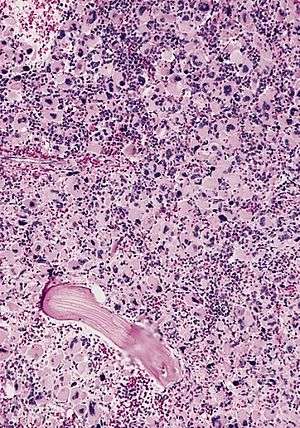

AML-M7, bone marrow section | |

Acute megakaryoblastic leukemia (AMKL) is a form of leukemia where a majority of the blasts are megakaryoblastic.[1]

It is classified under AML-M7 category of the French-American-British classification.[2]

In blood and bone marrow smears megakaryoblasts are usually medium-sized to large cells with a high nuclear-cytoplasmic ratio. Nuclear chromatin is dense and homogeneous. There is scanty, variable basophilic cytoplasm which may be vacuolated. An irregular cytoplasmic border is often noted in some of the megakaryoblasts and occasionally projections resembling budding atypical platelets are present. Megakaryoblasts lack myeloperoxidase (MPO) activity and stain negatively with Sudan black B. They are alpha naphthyl butyrate esterase negative and manifest variable alpha naphthyl acetate esterase activity usually in scattered clumps or granules in the cytoplasm. PAS staining also varies from negative to focal or granular positivity, to strongly positive staining. A marrow aspirate is difficult to obtain in many cases because of variable degree of myelofibrosis. More precise identification is by immunophenotyping or with electron microscopy (EM). Immunophenotyping using MoAb to megakaryocyte restricted antigen (CD41 and CD61) may be diagnostic.[10]